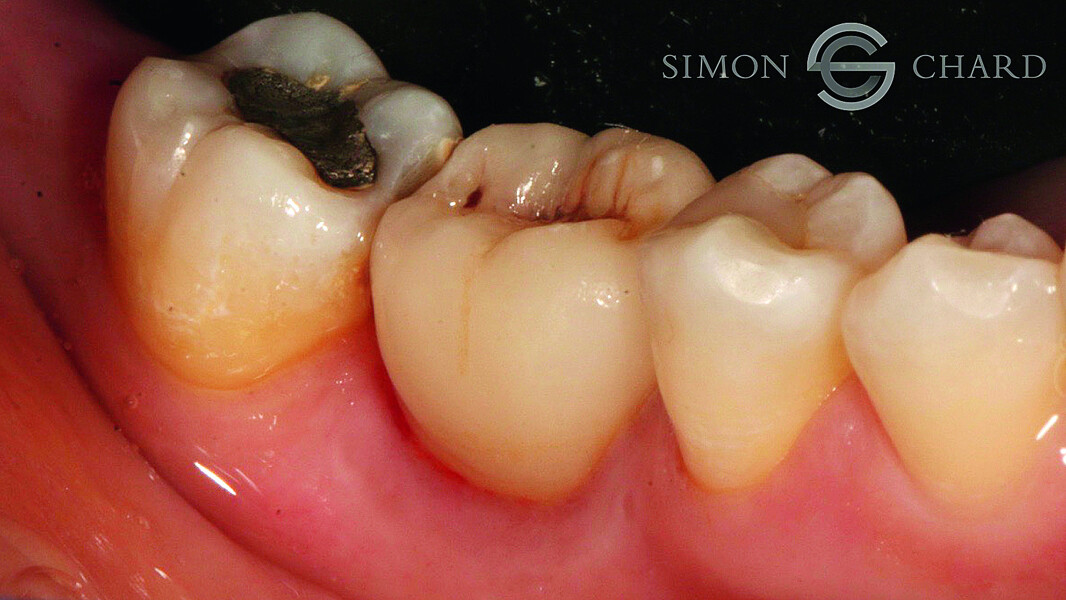

Implant restoration with CEREC